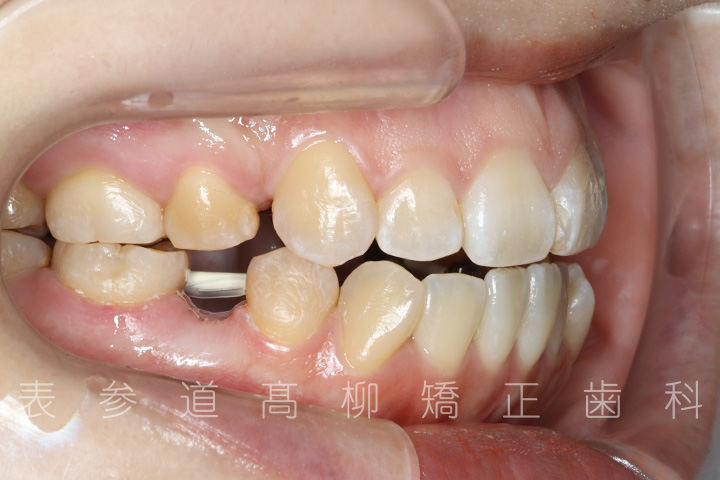

前歯のガタガタ感と開咬でお悩みの患者様の症例をご紹介いたします。

・前歯部開咬

・上下前歯部叢生(凸凹歯並び)